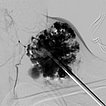

In the fluoroscopic control (lateral plane) after injection of 8 ml of polidocanol foam (3%, 1 : 4 foamed in air), the entire venous malformation is filled with the non-contrasting foam. The previously contained contrast medium is almost completely displaced by the sclerosing foam. Thus there is a good chance that the lesion will be very largely closed by the procedure.